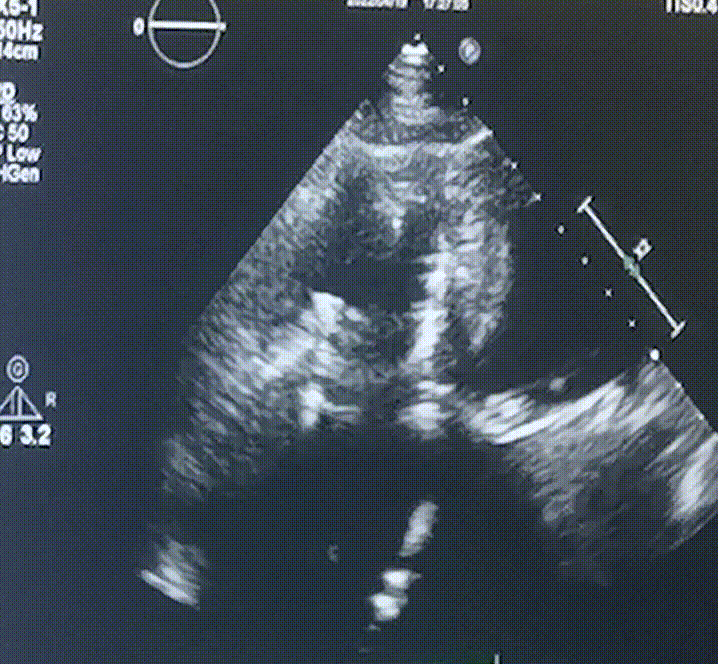

此次手術(shù)在全麻下進行,采用經(jīng)右側(cè)頸靜脈入路。術(shù)中在經(jīng)食道超聲和DSA的指引下多個維度精細調(diào)整輸送器角度,在達到正確位置后,逐步釋放瓣膜錨定裝置和盤片,最終完成瓣膜植入。術(shù)后患者右房壓明顯下降,術(shù)后超聲提示人工三尖瓣同軸性良好,瓣架固定牢靠,無反流和瓣周漏,血壓術(shù)后即刻上升20mmHg左右,手術(shù)后監(jiān)護室順利拔除氣管插管,3天后恢復良好,予以出院。

圖2.術(shù)后超聲